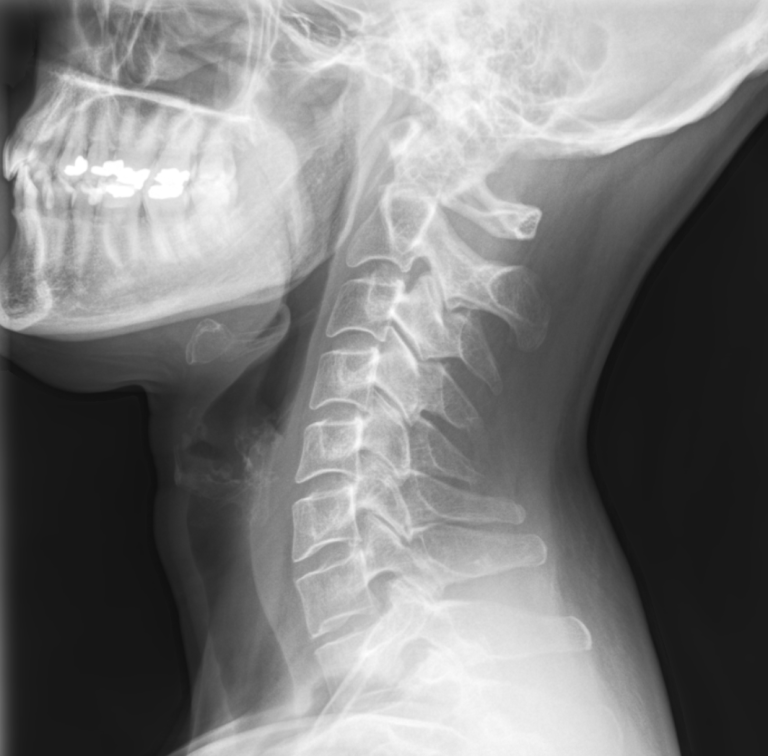

Die HalswirbelsĂ€ule â eine anfĂ€llige Stelle

Der Nacken bzw.anatomisch die HalswirbelsÀule (HWS) ist ein hochkomplexes System aus sieben Wirbeln, Bandscheiben, BÀndern und Muskeln.

Die HalswirbelsĂ€ule (HWS) ist unsere anatomische Schwachstelle, weil sie zwei gegensĂ€tzliche Aufgaben erfĂŒllen muss: maximale Beweglichkeit und hohe Traglast.

Die sieben filigranen Halswirbel mĂŒssen den Kopf tragen, der etwa 5 bis 6 kg wiegt. Anders als die BrustwirbelsĂ€ule (Rippen) hat die HWS dafĂŒr kein knöchernes Korsett. Sie ist allein auf die Muskulatur angewiesen. AuĂerdem ist der Hals eine vergleichsweise filigrane Stelle am Körper: Auf engstem Raum verlaufen hier RĂŒckenmark, Gehirn-Arterien und Nerven. Schon kleinste Verspannungen drĂŒcken sofort auf empfindliche Strukturen. DafĂŒr reicht schon Stress oder eine ungesunde Haltung am Schreibtisch. Bei Stress ziehen wir unbewusst die Schultern hoch. Diese Daueranspannung fĂŒhrt zur ĂbermĂŒdung der kleinen Nackenmuskeln.

Kurz gesagt: Die HWS ist der beweglichste, aber auch instabilste Teil der WirbelsÀule, der unter Fehlhaltung (wie dem Handynacken) schnell kapituliert.